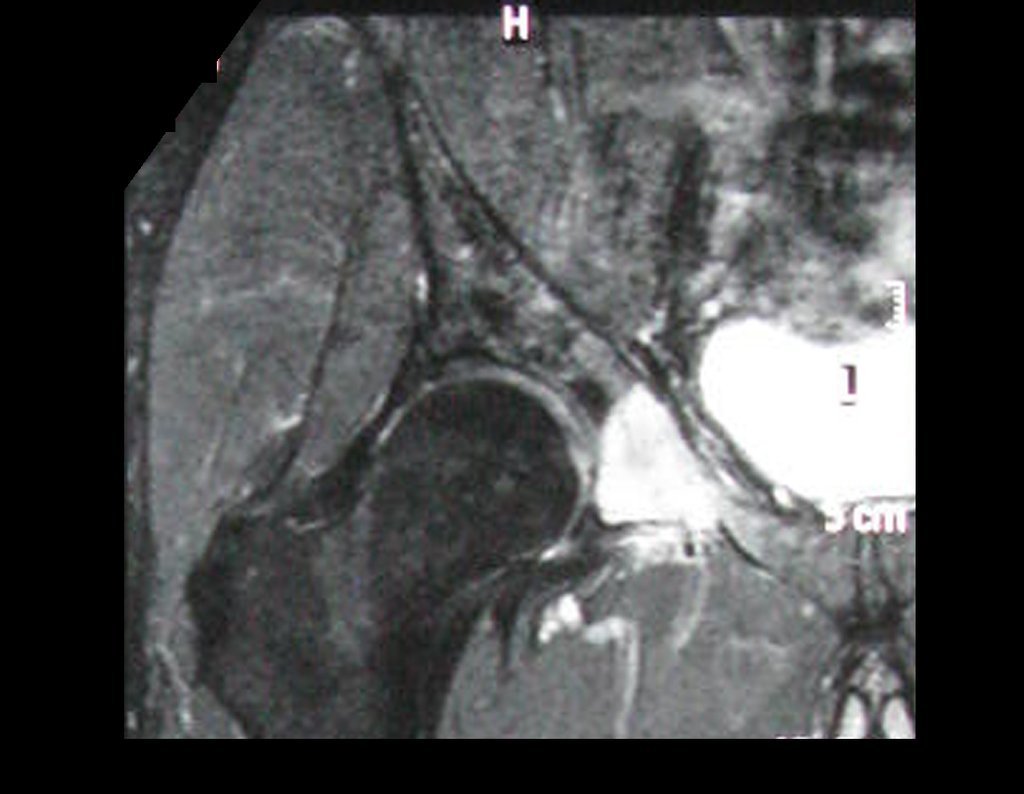

Kidney Cancer Metastasis. Hypernephroma bone metastasis, also known as metastatic kidney cancer to the bone, is a serious complication of kidney cancer. Hypernephroma, or renal cell carcinoma, is a common form of cancer that originates in the kidneys. When bone metastasis occurs, cancer cells spread from the kidneys to the bones, potentially affecting several areas of the skeleton.

This spread of cancer to the bones can cause a series of symptoms, such as persistent bone pain, pathological fractures and impaired mobility. Furthermore, bone metastasis from hypernephroma can lead to serious complications such as spinal cord compression that require immediate medical intervention.

Treatment of bone metastasis from hypernephroma generally involves a multidisciplinary approach, including surgery, radiotherapy, targeted therapy, and/or immunotherapy. The aim of treatment is to control the spread of cancer, alleviate symptoms and improve the patient’s quality of life.